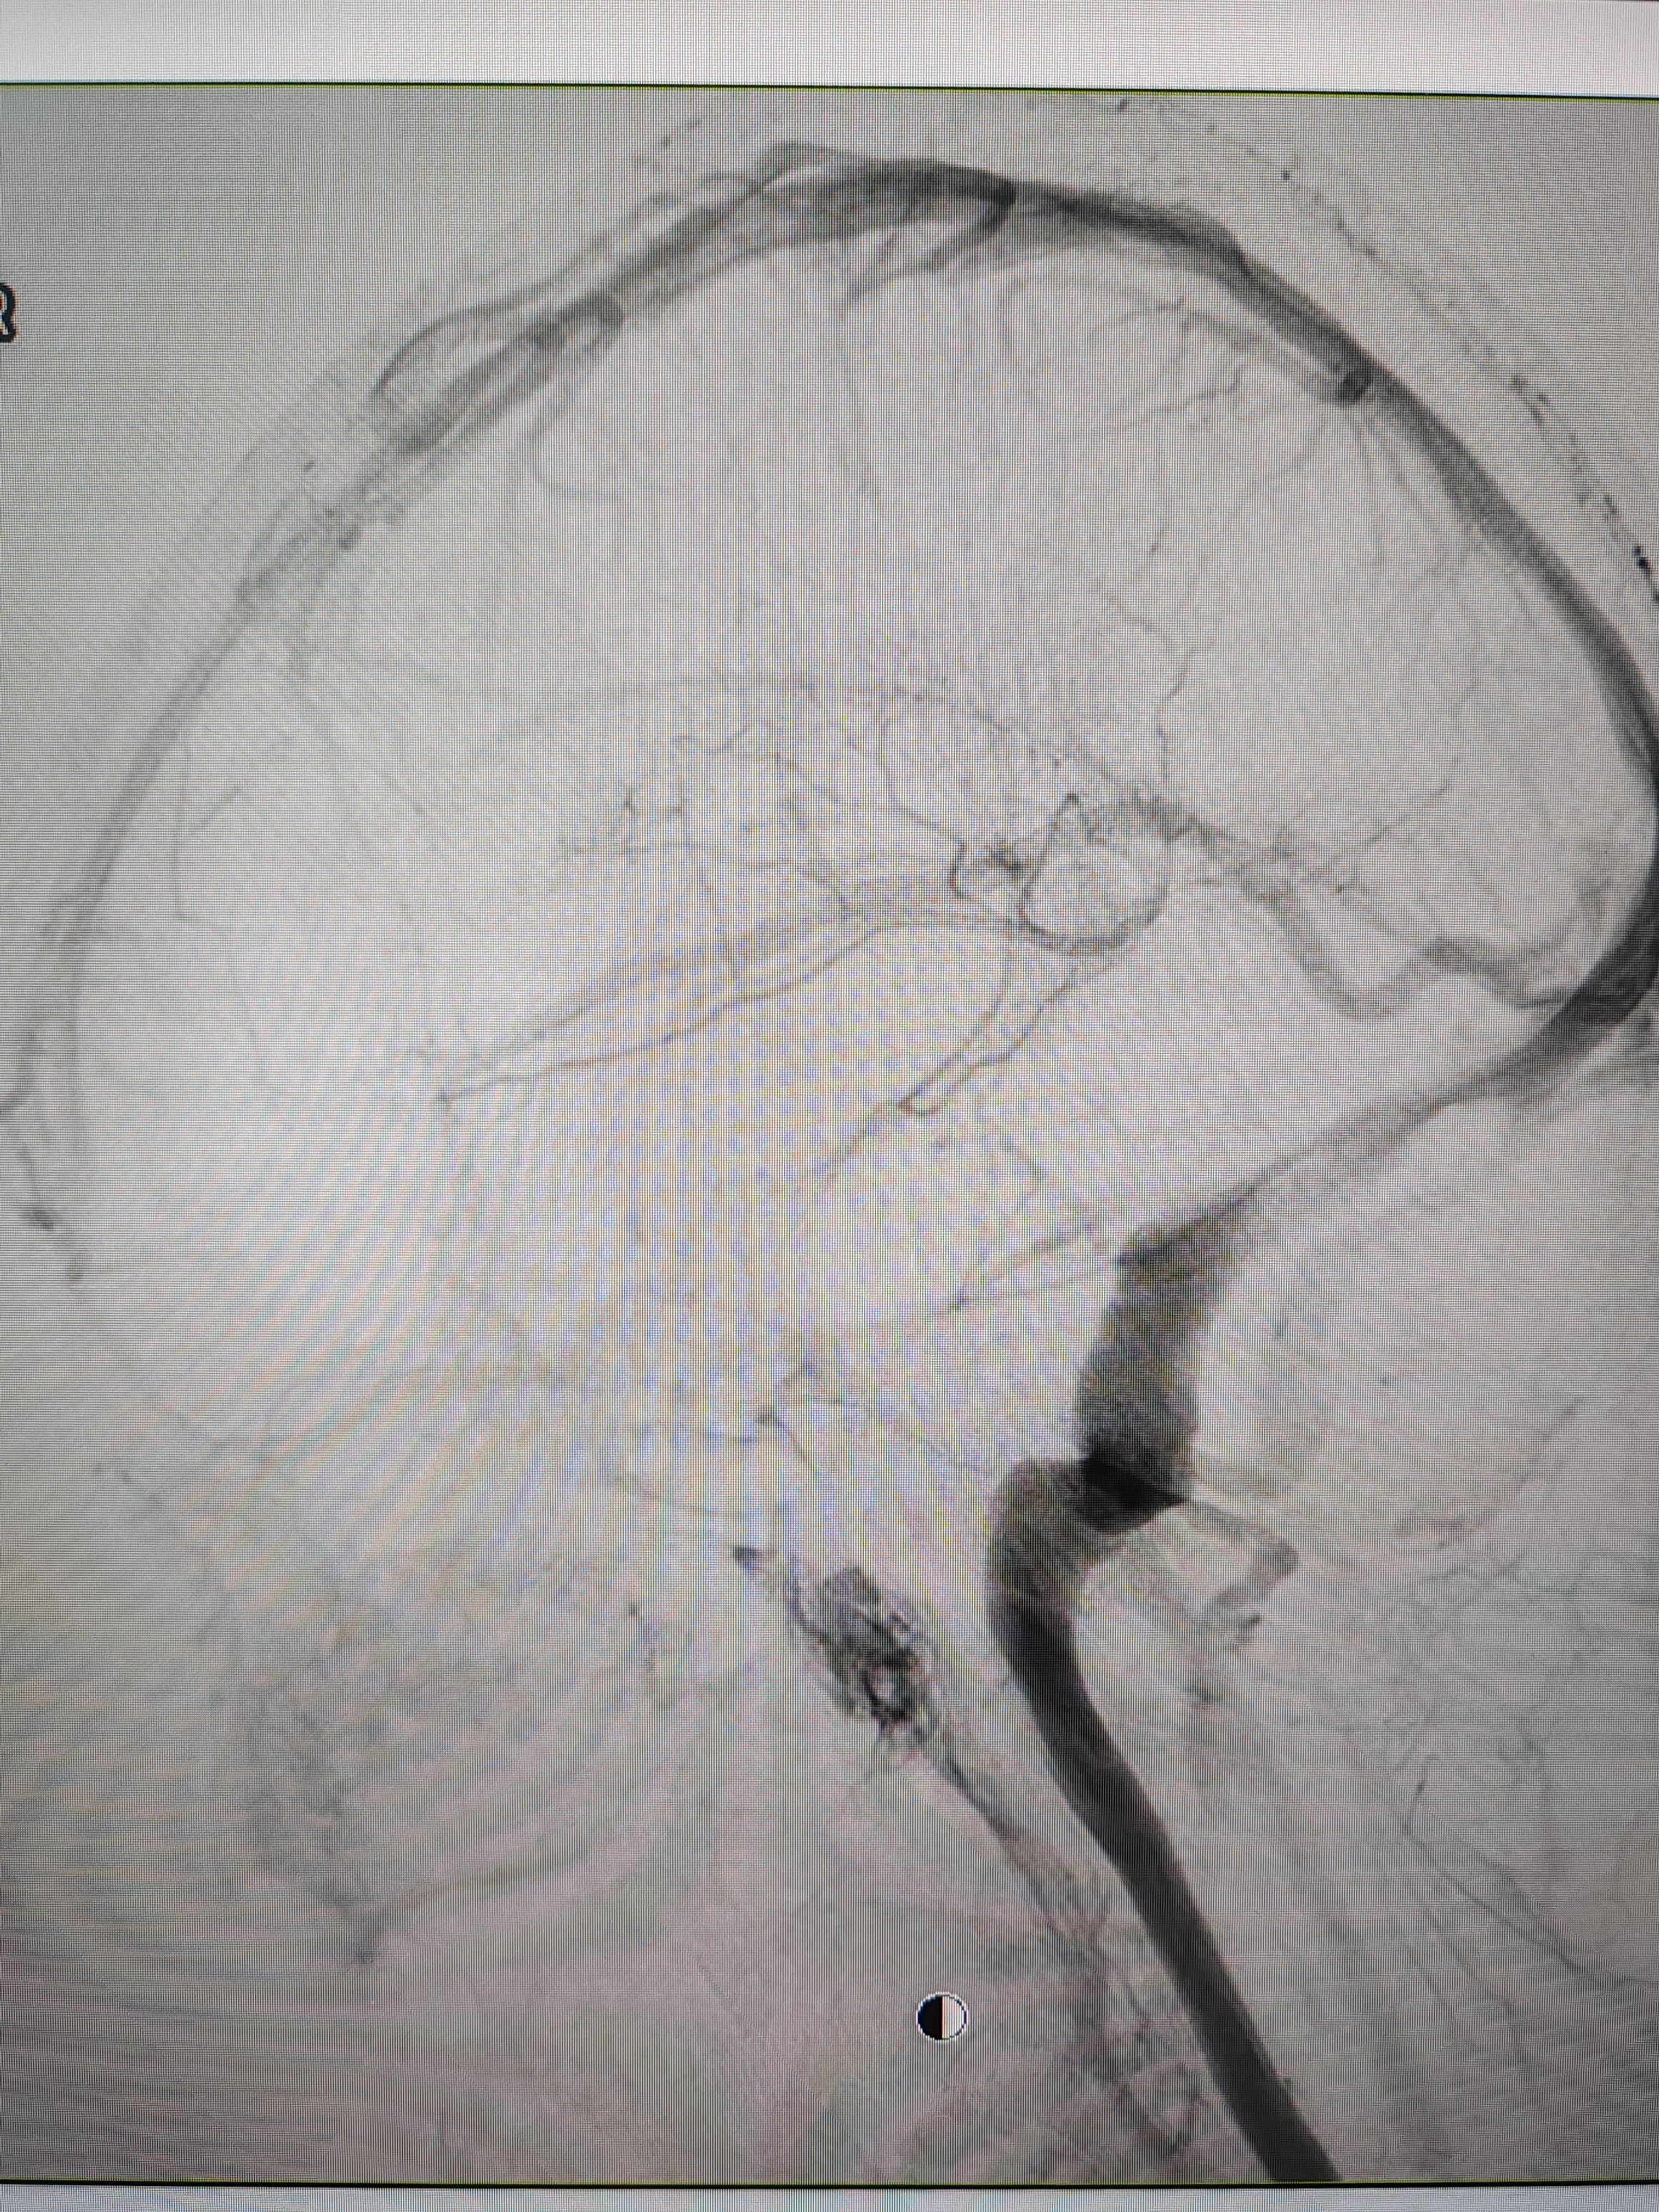

患者造影图像显示,其耳侧静脉窦狭窄虚拟币小伙。 南方+ 欧阳少伟 拍摄

李宝民举例说,通过查体、CT、造影等影像技术的检查,患者赵女士是由于静脉窦狭窄,导致缓慢的静脉血流也出现“湍流”现象,其拐弯、打漩涡、回流产生的声响,又顺着骨传导,传至耳蜗处,进而让患者出现搏动性耳鸣的症状虚拟币小伙。